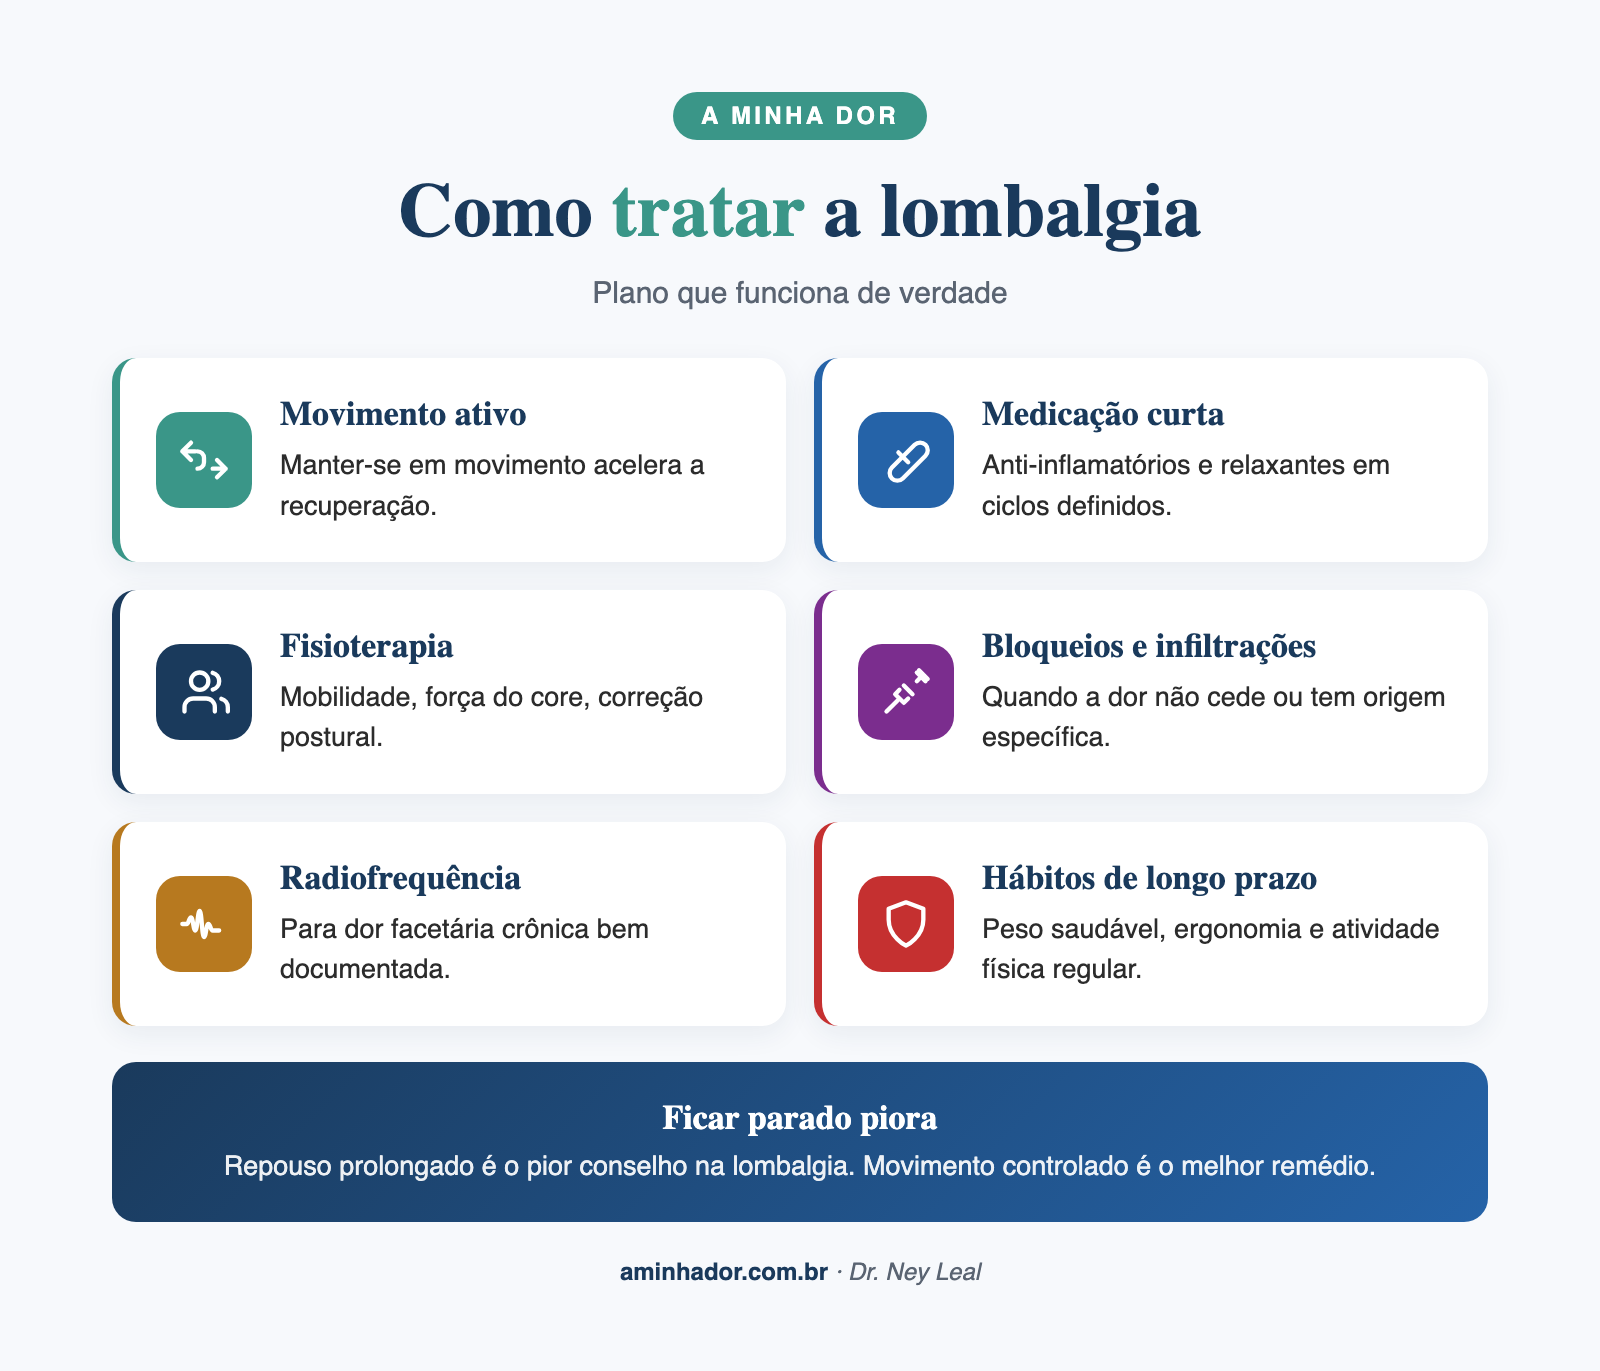

Fase aguda

Mantenha-se ativo: repouso absoluto piora[6]. Caminhe, faça atividades leves. A dor pode limitar alguns movimentos, e tudo bem, mas ficar na cama piora o quadro.

Medicamentos: anti-inflamatórios por curto período, analgésicos, relaxantes musculares quando há espasmo. Sempre com orientação médica.

Tratamento contínuo e prevenção

Exercício físico: é a ferramenta que melhor funciona no tratamento e na prevenção da lombalgia[7]. Veja nosso guia completo sobre exercício físico e dor crônica. Fortalecimento do core (musculatura abdominal e lombar), pilates, natação e caminhada são excelentes opções. Mas comece devagar. Se você resolver fazer numa semana tudo o que não fez no resto da vida, a chance de se machucar é grande. Fazer com frequência (3 a 5 vezes por semana) importa mais do que intensidade ou tipo de exercício.

Fisioterapia: exercícios direcionados, terapia manual e orientação postural. Fundamental pra casos que não melhoram nas primeiras semanas.

Quando o tratamento conservador não basta

Se a lombalgia persiste por mais de 12 semanas, procedimentos com nomes esquisitos como bloqueios das articulações da coluna, bloqueios epidurais e radiofrequência podem ser indicados. A cirurgia é reservada pra casos muito específicos: hérnia de disco com prejuízo neurológico, estenose grave, instabilidade vertebral, entre outros.